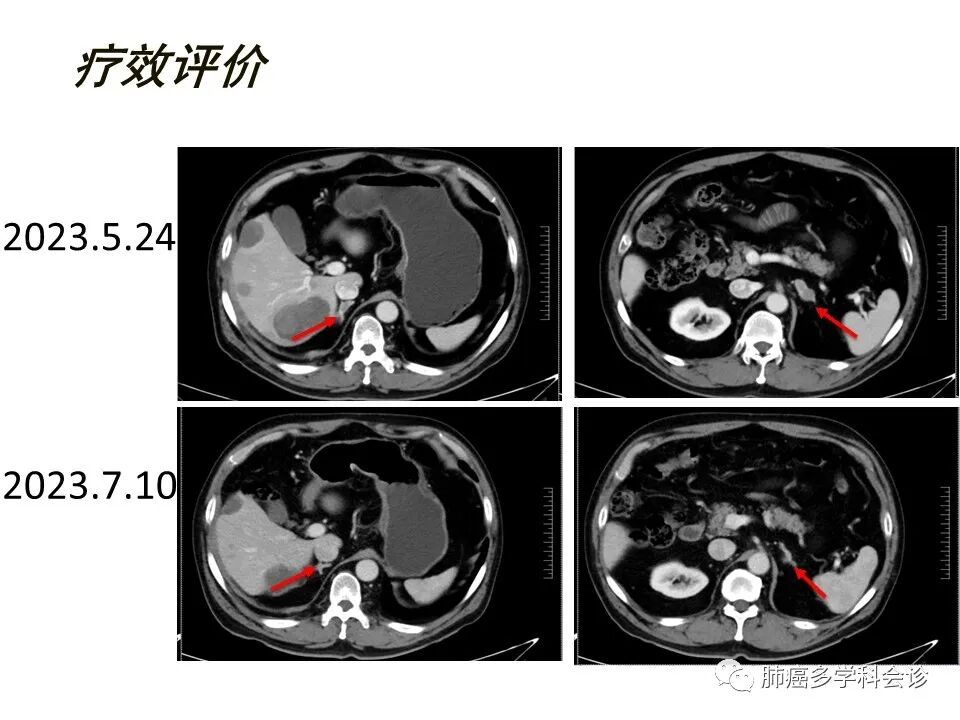

2023年5月24复查CThKb帝国网站管理系统

肺结节、肿块,考虑转移,较前2020.07.10片新发hKb帝国网站管理系统

前纵隔软组织结节,考虑转移,较前新发,右肺门肿大淋巴结,较前新发。hKb帝国网站管理系统

右侧胸廓入口处增多小淋巴节,考虑转移,较前新发,右侧胸膜结节增厚,较前稍进展。hKb帝国网站管理系统

肝脏多发转移考虑,较前新发hKb帝国网站管理系统

双侧肾上腺结节,转移可能,较前新发hKb帝国网站管理系统